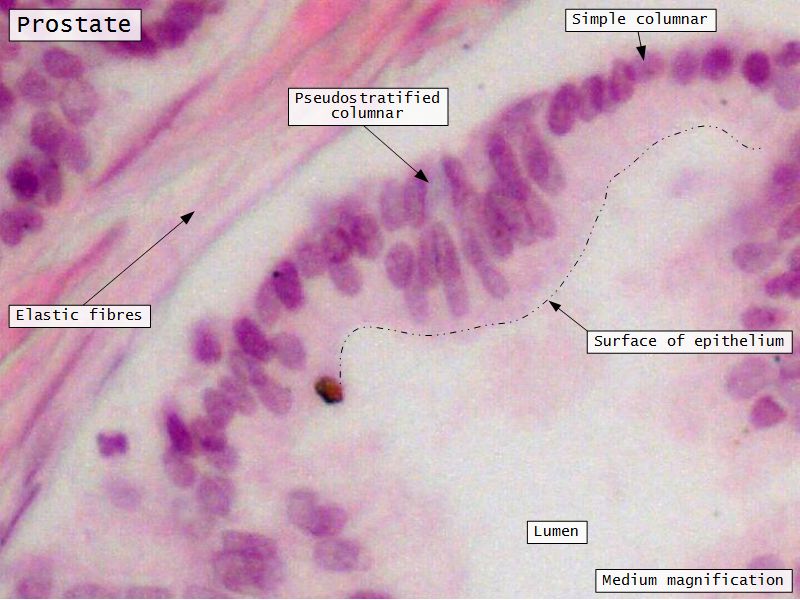

Prostate

Slide 80Prostate

Epithelium

- Simple columnar or

- Pseudostratified columnar

- Surrounded fibroelastic CT

- CT with rich vascular supply